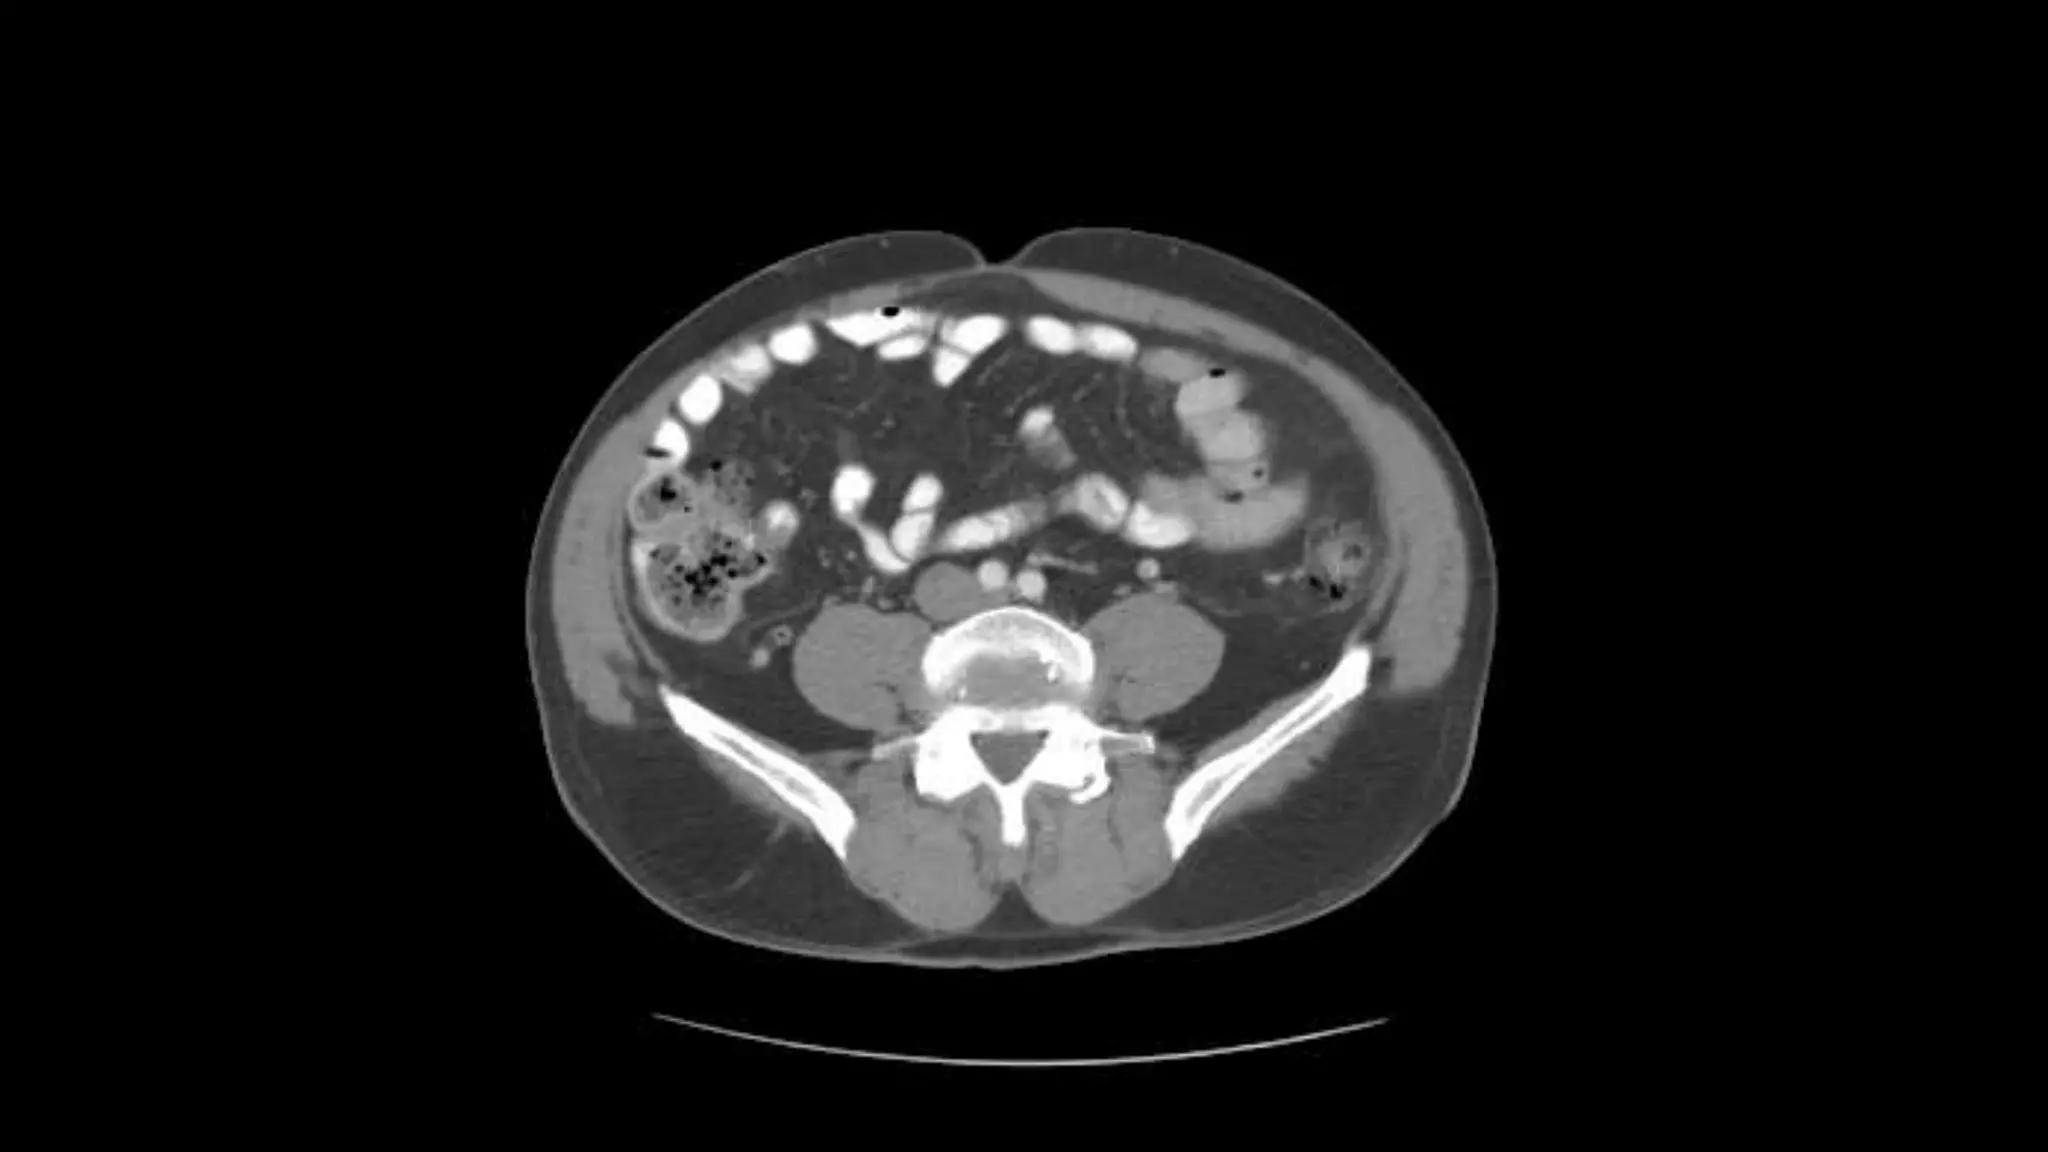

 In this sequence of images, we will label the abdominal vasculature.

The CT images are 5mm slices with soft tissue window settings. IV

Follow the IV contrast filled Aorta as we descend caudally. Branches and points

of interest will be noted.

Rt. and Lt.Kidneys

Renal Veins emptying into the IVC. We also see the right renal artery branching

off the Aorta, follow it down till you see it enter the right kidney. The Superior

Mesenteric Vein is outlined on the top of this image. If you follow the SMV up, you

will see it empty into the Portal Vein.

Here we see the right and left renal vein entering into the Inferior Vena Cava. We

Also see the left renal artery branching off the aorta and heading toward the left

kidney. Page up and down to trace these vessels.